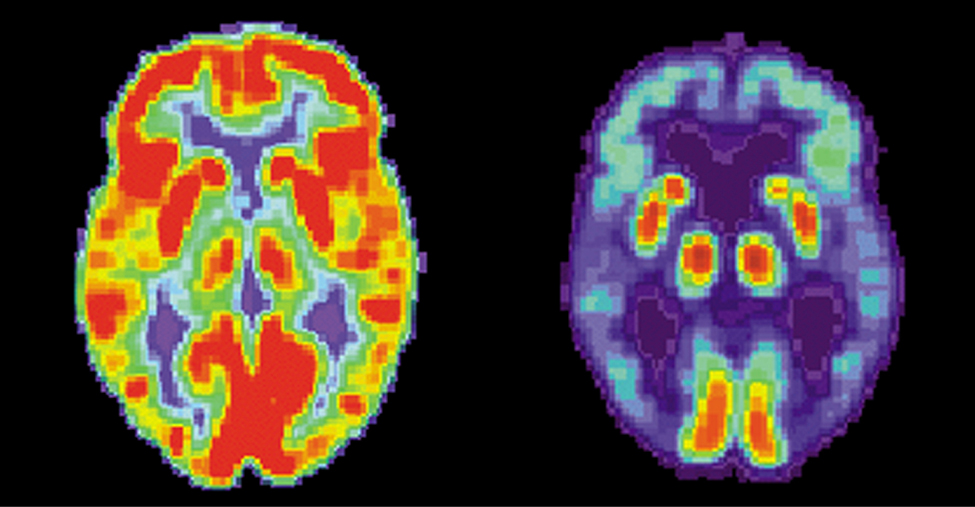

One of the most important uses of nuclear radiation is the location and study of diseased tissue. This application requires a special drug called a radiopharmaceutical. A radiopharmaceutical contains an unstable radioactive isotope. When the drug enters the body, it tends to concentrate in inflamed regions of the body. (Recall that the interaction of the drug with the body does not depend on whether a given nucleus is replaced by one of its isotopes, since this interaction is determined by chemical interactions.) Radiation detectors used outside the body use nuclear radiation from the radioisotopes to locate the diseased tissue. Radiopharmaceuticals are called radioactive tags because they allow doctors to track the movement of drugs in the body. Radioactive tags are for many purposes, including the identification of cancer cells in the bones, brain tumors, and Alzheimer’s disease (Figure 10.27). Radioactive tags are also used to monitor the function of body organs, such as blood flow, heart muscle activity, and iodine uptake in the thyroid gland.

Two images of brains are shown. The one on the left has many red and orange areas and some blue areas. The one on the right is mostly blue with very small areas in red and yellow.

Figure 10.27 These brain images are produced using a radiopharmaceutical. The colors indicate relative metabolic or biochemical activity (red indicates high activity and blue indicates low activity). The figure on the left shows the normal brain of an individual and the figure on the right shows the brain of someone diagnosed with Alzheimer’s disease. The brain image of the normal brain indicates much greater metabolic activity (a larger fraction of red and orange areas). (credit: modification of works by National Institutes of Health)

PET scans are especially useful to examine the brain’s anatomy and function. For example, PET scans can be used to monitor the brain’s use of oxygen and water, identify regions of decreased metabolism (linked to Alzheimer’s disease), and locate different parts of the brain responsible for sight, speech, and fine motor activity